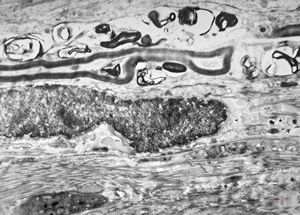

F, 8y. | metachromatic leukodystrophy … n. suralis